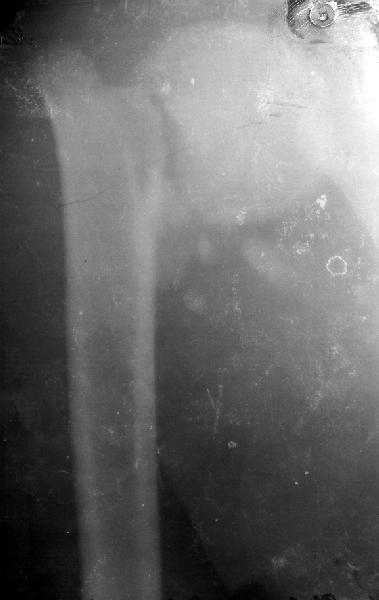

Мужчина 25 лет 16 августа 2002 г. в автоаварии получил перелом шейки плеча (снимок 1); 5 сентября в городской больнице выполнен остеосинтез пластинкой (снимок 2).К настоящему времени попал к нам на разработку ввиду выраженной контрактуры плечевого сустава. В течение последнего месяца беспокоят умеренные боли в области плечевого сустава, усиливающиеся при разработке, еще и торчит край пластинки. Нынешняя рентгенологическаякартина на снимках 3 и 4. Головка плеча уменьшается, сращение сомнительное.Кроме удаления пластинки, что еще на сегодня целесообразно сделать?Заранее спасибо.

1.Операция сделана через 3 недели после перелома, когда в месте перелома был уже фиброз - так это происходит нормально у молодого 25 лет человека и так мне видно на Х-фильме АР ( антеро-постериор). Решение оперировать в этот период абсолютно непонятно. Если решил сделать внутреннюю фиксацию, делай её до конца первой недели, а лучше в первые 3-4 дня. Решил лечить

консервативно - проводи это лечение до явных признаков сращения или ложного сустава. После 3 недель, для осуществления внут. фиксации уже необходимо открыть и зачистить до живой кости фрагменты перелома, т.е. проводить внутри-суставную операцию, очень проблематичную для судьбы плечевого сустава. По-моему, наложению пластины зачистка перелома не предшествовала.

2.Пластинка , на мой взгляд, худшее решение для перелома шейки плеча. Сама пластинка слишком груба и массивна, целая слесарня в очень чувствительной для повреждений суставе.